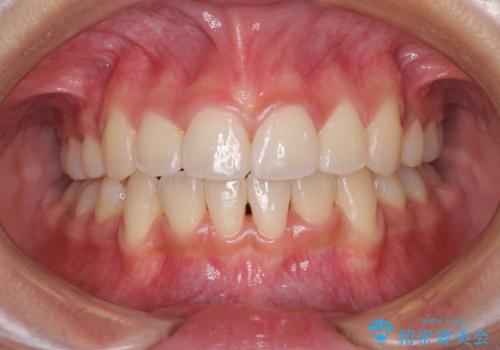

半年ほどで前歯のデコボコは改善され、汚れの溜まりやすさは解消されました。

抜歯スペースを閉じるために期間がかかりましたが、当初予定通り2年強で終えることができました。